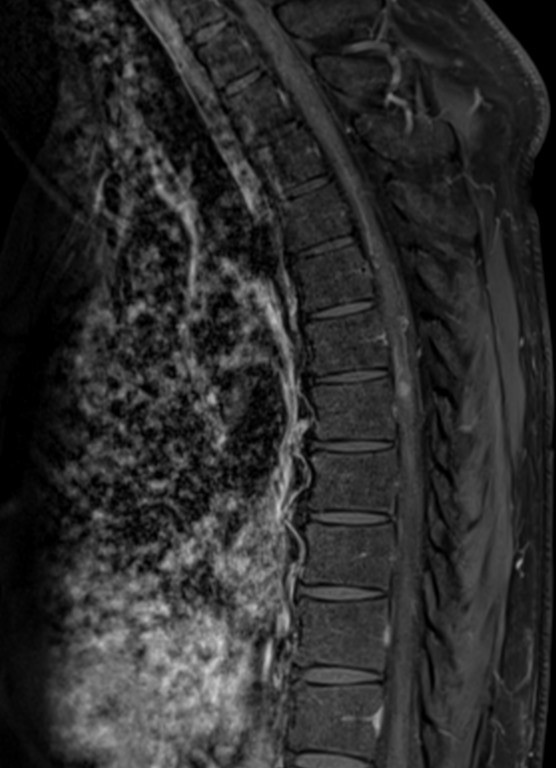

Resonancia Magnética de Columna

Envíado por Dr. José Rafael Chang Calero